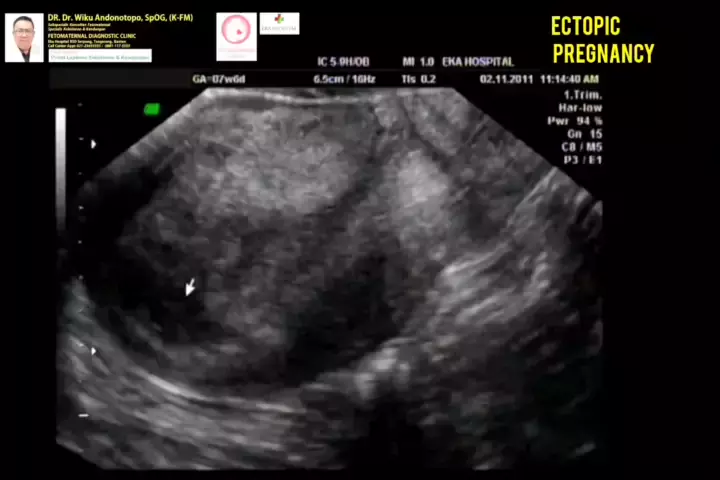

Kehamilan Ektopik 7-8 minggu #ectopicpregnancy #ectopicpregnancysurvivor #kehamilanektopik #kehamilanektopikterganggu #hamildiluarkandungan #usgfetomaternalekahospitalbsd #konsultanfetomaternalekahospitalbsd #konsultanfetomaternalpontianak #konsultanfetomaternalsemarang #usgfetomaternalpontianak #usgfetomaternalsemarang #fetomaternal #spog #fetomaternalsemarang # #polikandunganekahospitalbsd #drwikuandonotopo #ekahospitalbsd #fetomaternaltangerang